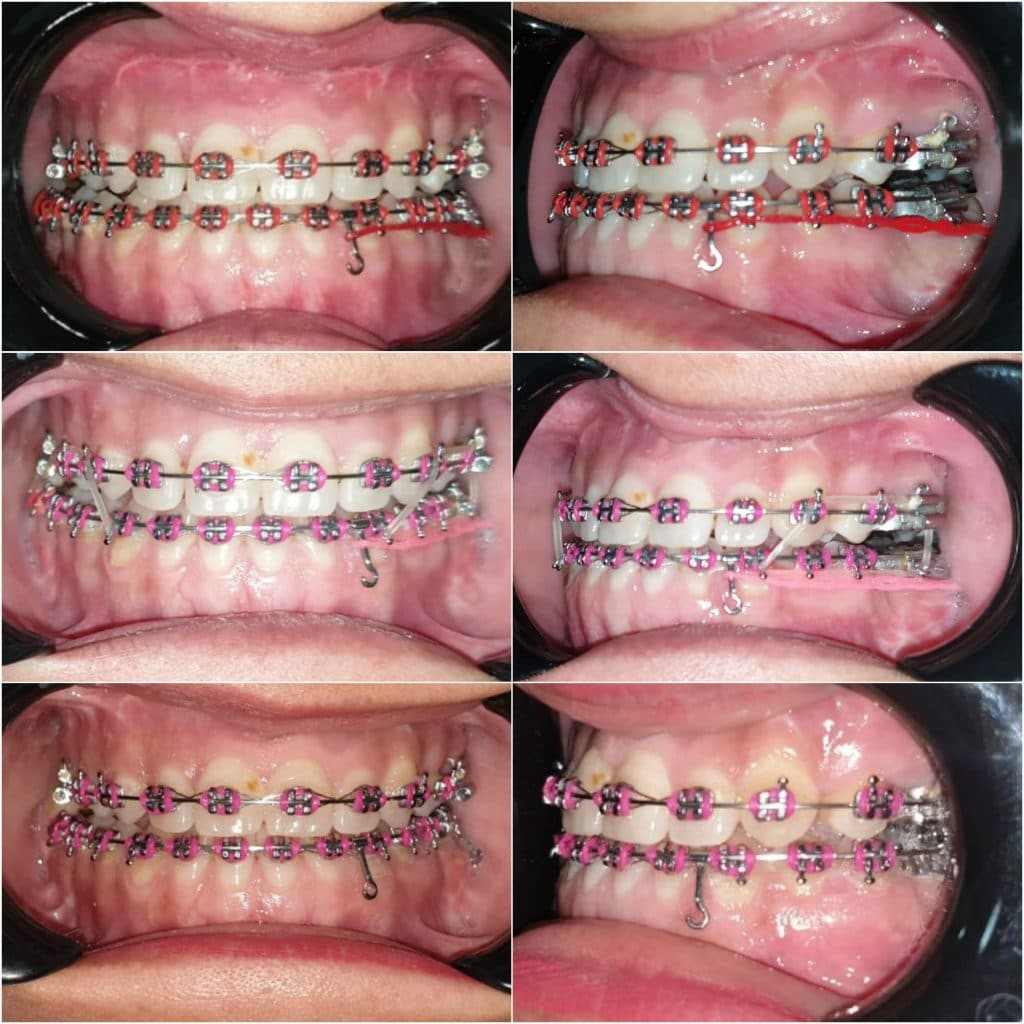

- A . Orthodontic preparation : including extraction of UL 4 , leveling and alignment , decompensation , arch coordination , creating surgical wafers for bimaxillary surgery and referred to the surgeon

* complication : the case dismissed after surgery without instructions to keep using the wafer along with elastics , also multiple debondings happened during the surgery , so patient came to me 3 weeks after surgery with posterior openbite , progressing shift of lower midline towards the right side , and cl III canines in left side

*managment : intermaxillary elastics , and unilateral buccal shelf TAD inserted in left side to distalize this segment to obtain cl I canine , and coincident midline .